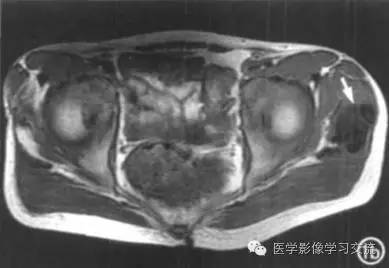

其它检查结果如下:

MRI具有多参数、多序列、多方位成像的功能,可根据信号判断组织成分; 由于肿瘤主要由纤维包膜包裹的钙化沉积物及淡黄色乳糜状液体组成,内有纤维间隔,

因此 T1WI肿瘤呈不均匀低信号, T2WI 呈不均匀高信号; 肿瘤包膜呈长 T1 、长 T2 信号。MRI 对观察肿瘤边缘及肿瘤与关节、骨骼的关系价值大,能多方位显

示病变不累及关节或骨骼,对诊断有较大帮助。